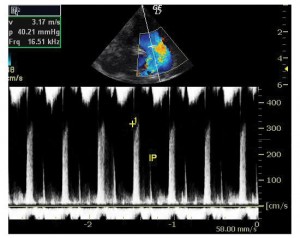

Ecocardiografia a depistat o malformaţie cardiacă congenitală simplă: defect septal interatrial (DSA) larg, tip ostium secundum, cavităţi drepte mult dilatate (atriu drept, ventricul drept, artera pulmonară), hipertensiune pulmonară (presiune pulmonară medie: 40 mmHg), defect septal interventricular muscular apical mic, insuficienţă mitrală uşoară (Figura 1, 2).

Figura 2. Ecocardiografie transtoracică incidenţă parasternal ax scurt: dilataţie de arteră pulmonară, insuficienţă pulmonară (v max protodiastolică 3,12m/s).

Evoluţia imediat postoperatorie a fost fără complicaţii, sugarul revenind în secţia de cardiologie pentru recuperare. Condiţiile generale erau ameliorate, notându-se chiar şi o uşoară creştere ponderală. Controalele ecocardiografice succesive au evidenţiat însă o dilataţie graduală a ventriculului stâng cu afectarea progresivă a funcţiei sistolice şi apariţia ulterioară a unei insuficienţe mitrale severe. Nu a putut fi vizualizată originea arterei coronare stângi din aortă, în plus notându-se flux bidirecţional în artera coronară descendentă anterioară la examenul Doppler color, ridicând suspiciunea de origine anormală a arterei coronare stângi (Figura 3). Presiunea pulmonară se redusese semnificativ (presiunea pulmonară medie a scăzut de la 40 mmHg la 21 mmHg), iar la nivelul septului interatrial nu exista şunt rezidual. Electrocardiograma evidenţia semne de ischemie miocardică, inexistente pe electrocardiogramele de dinainte de intervenţie: segment ST subdenivelat descendent în precordialele stângi şi unde T negative simetrice în precordialele drepte (Figura 4).

Figura 3. Ecocardiografie transtoracică incidenţă parasternal ax scurt: origine anormală a arterei coronare stângi. Ao: aortă, P: pulmonară, C: artera coronară.